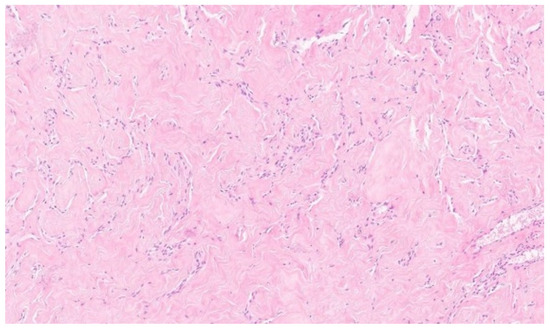

The histopathological examination confirmed the diagnosis of pseudoangiomatous stromal hyperplasia (PASH). The specimen was described as a solid, light gray-to-yellow tumor measuring 11 × 10 × 4.8 cm3, with the capsule preserved and intact (Figure 2 and Figure 3).

Microscopically, the hallmark of PASH is the presence of slit-like spaces resembling vascular channels, lined by spindle cells, without endothelial markers (CD31–), but with positive CD34 expression, which was also confirmed in our case [4,16].

Figure 3. Histological images of the PASH. Multiple interconnected slit-like pseudoangiomatous spaces, lined by spindle-shaped cells and separated by thick, hyalinized collagen bundles. H and E, 10×.